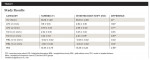

Implant primary stability: Mean insertion torque values were 36.19 ± 1.69 and 83.33 ± 4.99 Ncm for T and INV groups, respectively. The majority of implants (86%) in the T group were <50 Ncm whereas 71% of implants in the INV group attained ≥80 Ncm ITV with 57% reaching 100 Ncm.

LPD: Mean labial plate thickness was 1.18 ± 0.16 and 2.84 ± 0.16 mm at L1; 0.79 ± 0.14 and 2.56 ± 0.20 mm at L2 for T and INV groups, respectively.

TID: Mean CI-CI distance was 2.52 ± 0.18 and 3.06 ± 0.12 mm for T and INV groups, respectively. Mean CI-LI distance was 1.44 ± 0.11 and 2.40 ± 0.19 mm for T and INV groups, respectively.

MBL: Mean MBL between CI-CI was -0.02 ± 0.02 and -0.06 ± 0.02 mm for T and INV groups, respectively. Mean MBL between CI-LI was -1.06 ± 0.40 and -0.04 ± 0.02 mm for T and INV groups, respectively.

PES: The mean PES was 10.33 ± 0.79 for the T group and 13.29 ± 0.26 for the INV group.

Statistically significant differences were found between groups within each category except for CI-CI distance and MBL CI-CI (P > .05) (Table 1).